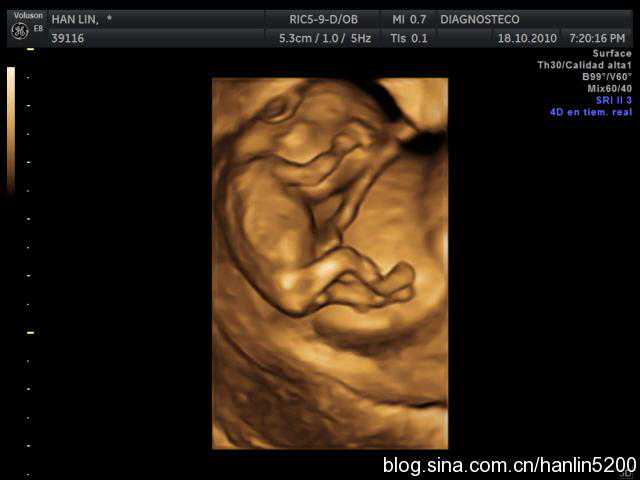

最后来个可爱的四维照!

有没有觉可爱到爆!